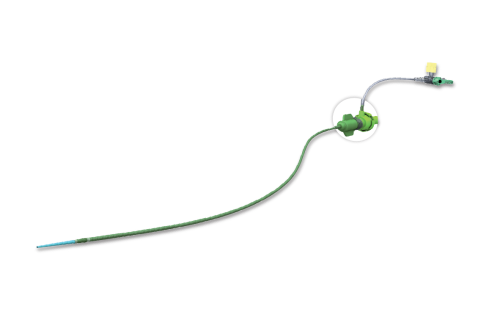

Na área de Cardiologia Intervencionista, fornecemos dispositivos de ponta, como stents, cateteres e balões, que são essenciais para a realização de angioplastias e outros procedimentos cardíacos minimamente invasivos. Nossos produtos são projetados para oferecer máxima eficiência e segurança, contribuindo para a rápida recuperação dos pacientes e a redução de complicações pós-operatórias.

Em Cirurgia Vascular, Endovascular e Radiologia Intervencionista oferecemos uma ampla gama de soluções, incluindo enxertos endovasculares, cateteres de trombectomia e dispositivos de embolização. Esses produtos são vitais para o tratamento de doenças vasculares complexas, como aneurismas e tromboses, proporcionando aos profissionais de saúde as ferramentas necessárias para intervenções precisas e eficazes.

Além disso, fornecemos soluções para o tratamento de feridas que promovem a cicatrização eficiente e segura para os pacientes. Nossos dispositivos de Terapia por Pressão Negativa são projetados para criar um ambiente ideal de cura, reduzindo o risco de infecções e acelerando o processo de cicatrização. Essas soluções são amplamente utilizadas em feridas crônicas,